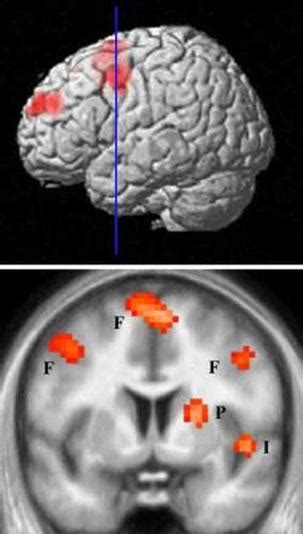

So, what’s really going on in our heads when we feel hate ? It’s a complex cocktail of emotions and psychological processes, guys. At its core, hate often arises from a perceived threat, injustice, or deep hurt. Our brains are wired for survival, and when we perceive a threat, whether it’s real or imagined, our primal instincts kick in. This can lead to a strong, negative emotional response, which, if left unaddressed, can fester into hate. Think about situations where you’ve experienced betrayal. That sting of being wronged can trigger a powerful defensive mechanism, leading to feelings of resentment and, eventually, hate. This is particularly true when the betrayal comes from someone we trusted. The psychological impact of such experiences can be profound, leading to a breakdown of trust and a strong desire to distance ourselves from the source of pain. Furthermore, cognitive biases play a huge role. We tend to seek out information that confirms our existing beliefs, a phenomenon known as confirmation bias. If we already have negative feelings towards someone or a group, we’re more likely to notice and remember their negative actions, while ignoring or downplaying any positive contributions they make. This creates a feedback loop that intensifies our hate. Group dynamics also contribute significantly. When we identify with a particular group, we often develop an “us vs. them” mentality. This in-group favoritism and out-group derogation can fuel collective hate, especially in times of conflict or social tension. The media and societal narratives can also shape our perceptions, amplifying existing prejudices and fostering new ones. It’s like a ripple effect; one person’s prejudice can influence others, creating a widespread sense of animosity. Understanding these psychological underpinnings is not about justifying hate, but about recognizing the mechanisms that drive it. This awareness is the first step toward disarming these automatic responses and making more conscious, compassionate choices. It’s about peeling back the layers of this intense emotion to understand its origins and how it functions within us. By doing so, we can begin to interrupt the cycle and cultivate healthier emotional responses. This is where the real work begins – not in suppressing these feelings, but in understanding their source and learning to manage them effectively, transforming them into something more constructive. This understanding is key to unlocking our potential for empathy and building stronger, more positive relationships with others. The more we grasp the ‘why’ behind our feelings, the better equipped we are to choose our reactions and steer clear of destructive paths.